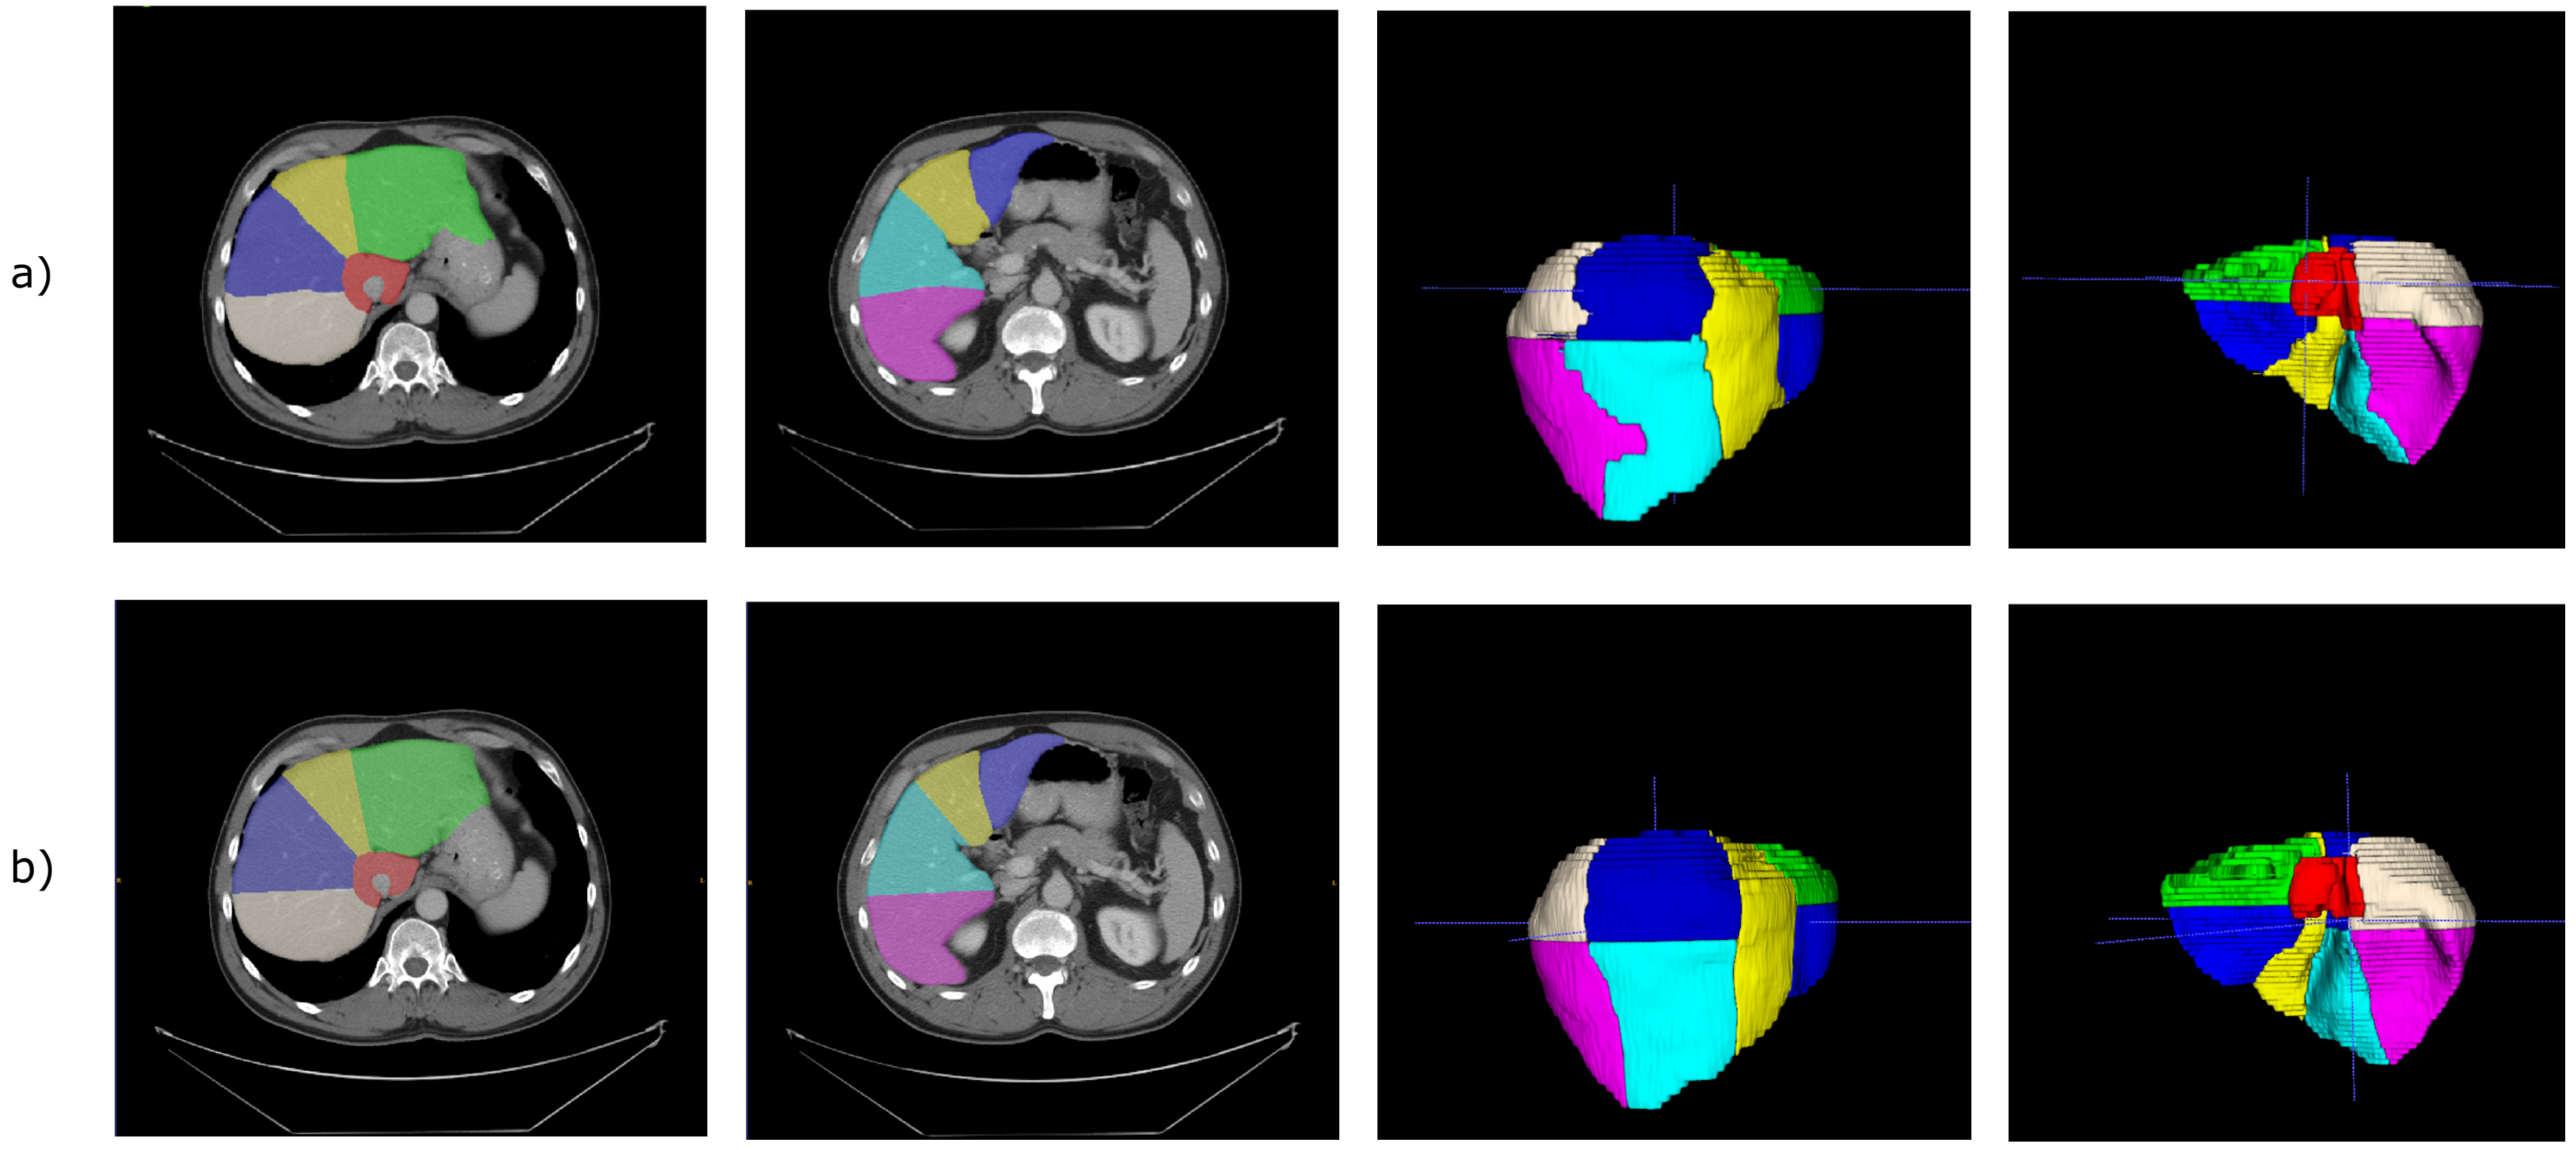

Experimental results are reported in Table 3, Table 4, Table 5 and Table 6, for models trained with , , , and , respectively. Figure 5 shows the segmentation obtained for a single CT scan, adopting with .

Figure 5.

(a) Prediction obtained from the 2.5D V-Net trained with our formulation of the focal Dice loss. For these images, the model was trained with with . (b) Corresponding ground-truth.